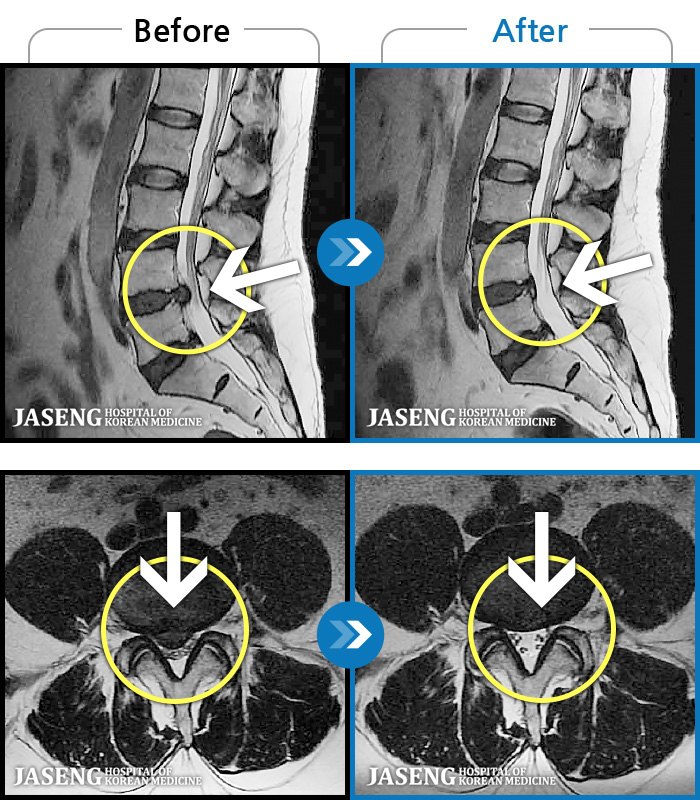

123 MRI ũ ʸ Ȯϼ.